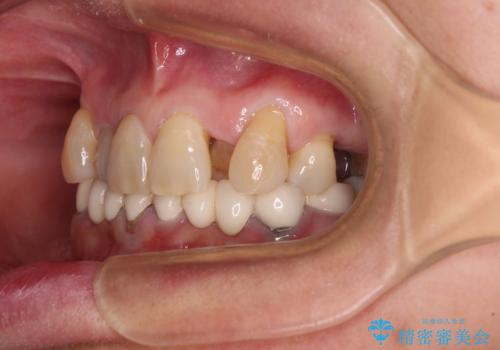

- 常に外れている下顎のブリッジと、前歯のデコボコと色を気にして来院された患者様です。

前歯のデコボコおよび奥歯の咬み合わせを改善するために、上顎左右の小臼歯を欠損スペースを利用して歯列を整え、矯正治療後に気になる上下前歯などをオールセラミッククラウンで美しく仕上げていくこととしました。